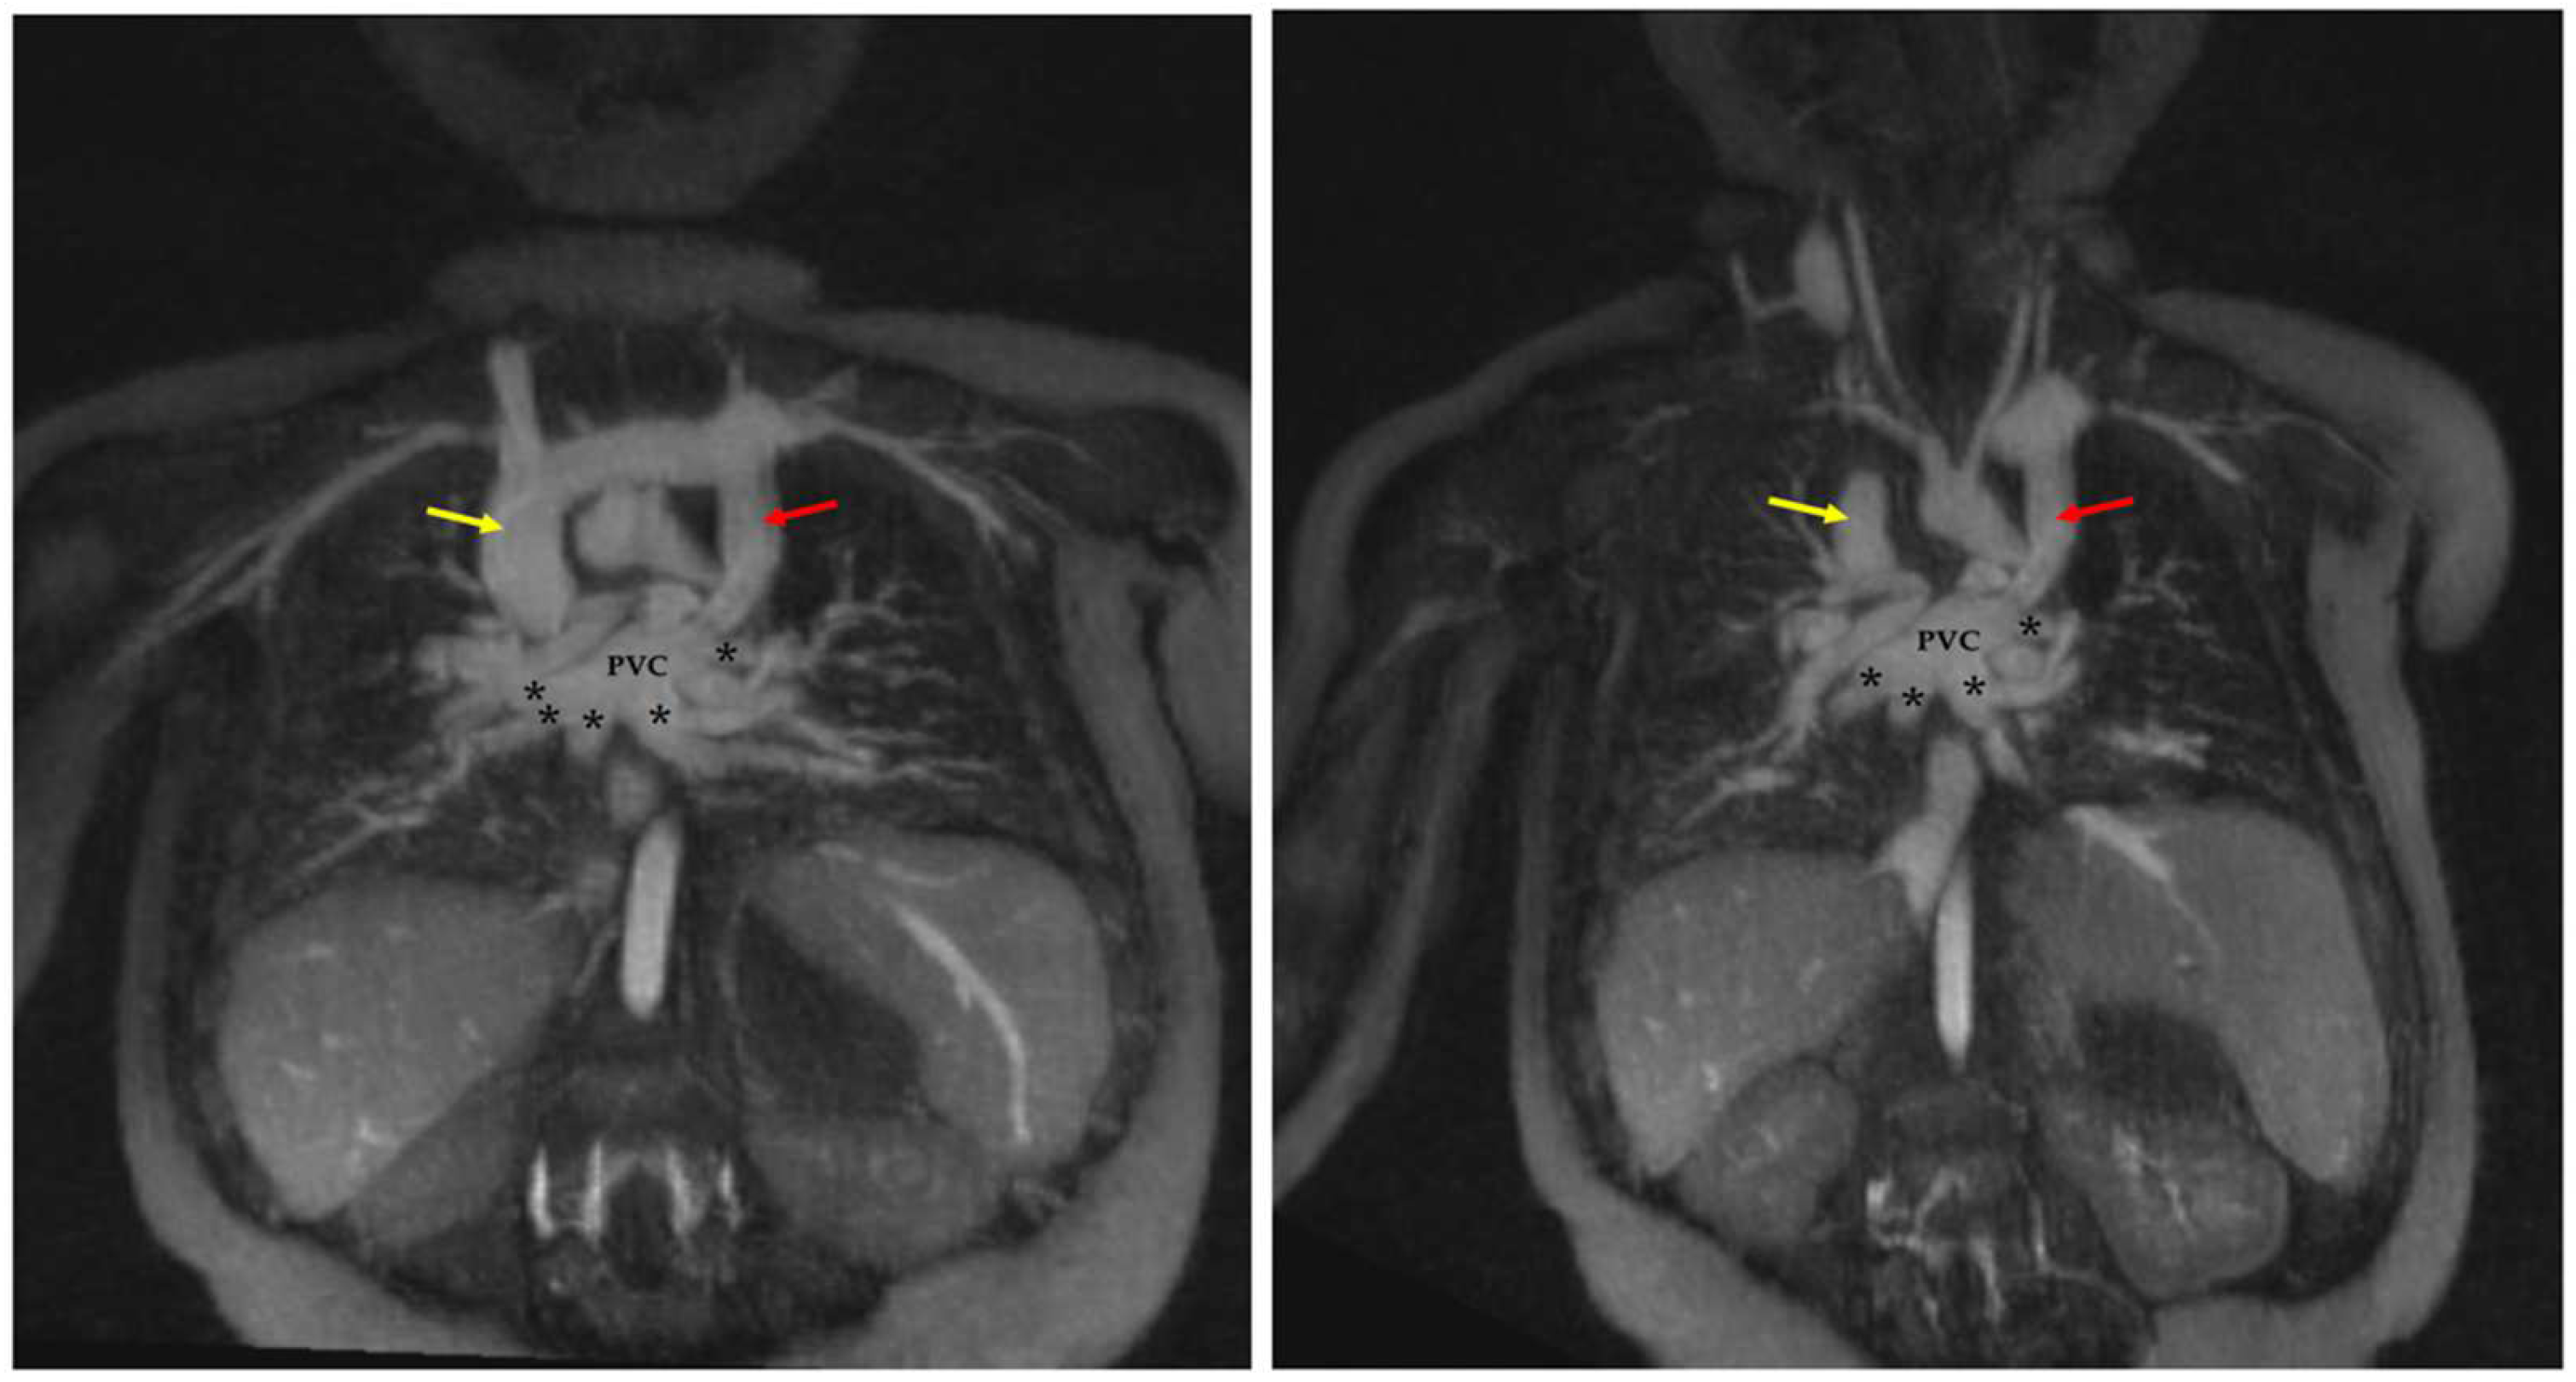

4.1.1. Total Anomalous Pulmonary Venous Connection (TAPVC)

4.1.2. Pulmonary Vein Stenosis

| TAPVC | FE steady-state imaging allows both the individual pulmonary veins and the abnormal systemic venous connection(s) to be visualized simultaneously in a single acquisition without the need for a timing bolus. |